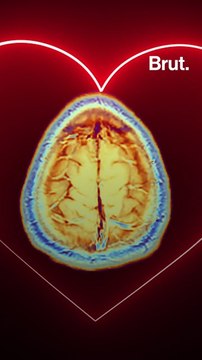

On m'a annoncé une espérance de vie comprise entre 15 et 20 mois . Gauthier a 52 ans et il est atteint d'un cancer du cerveau : le glioblastome, une tumeur agressive de stade 4. Mais comment fait-on pour vivre normalement quand on apprend une nouvelle comme ça ? On l’a rencontré avec sa famille, plus de 20 mois après le diagnostic.